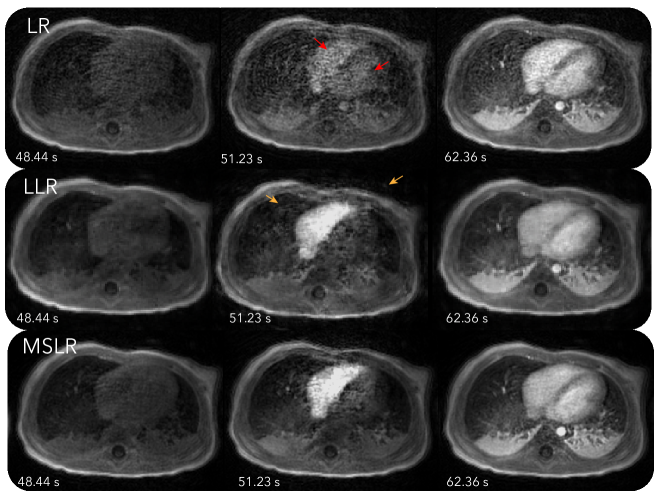

Figure 2 and Video S2, S3, and S4 show reconstruction results with LR, LLR and MSLR. As pointed by the red arrows, reconstruction with LR shows unrealistic dynamics, with contrast enhancing in both left and right ventricles at the same time. The other reconstructions show contrast enhancing first in the right ventricle then the left ventricle, which is physiologically correct. On the other hand, LLR displays more flickering temporal artifacts, which can be seen more visibly from Video S3. These artifacts are also pointed out by the orange arrows in figure. MSLR achieves a balance between representing contrast enhancement dynamics and reducing artifacts.

In Figure 2, we compared the effect of different LR modelings. Consistent with observations in [34, 5], LR has difficulty representing spatially localized dynamics, and exhibits temporal blurring of contrast enhancements in the ventricles. LLR is able to depict spatially localized dynamics well and show distinct contrast enhancements in the left and right ventricles. However, compared to MSLR, LLR has more spurious temporal artifacts. Because LR and LLR are subsets of MSLR, MSLR in principle can always perform better with the suitably tuned regularization parameters. The purpose of the experiment is to show that with a fixed regularization relationship between scales described in Equation (6), MSLR can still represent dynamics with the appropriate scale. This is also supported qualitatively in the MSLR decomposition shown in Figure 3.